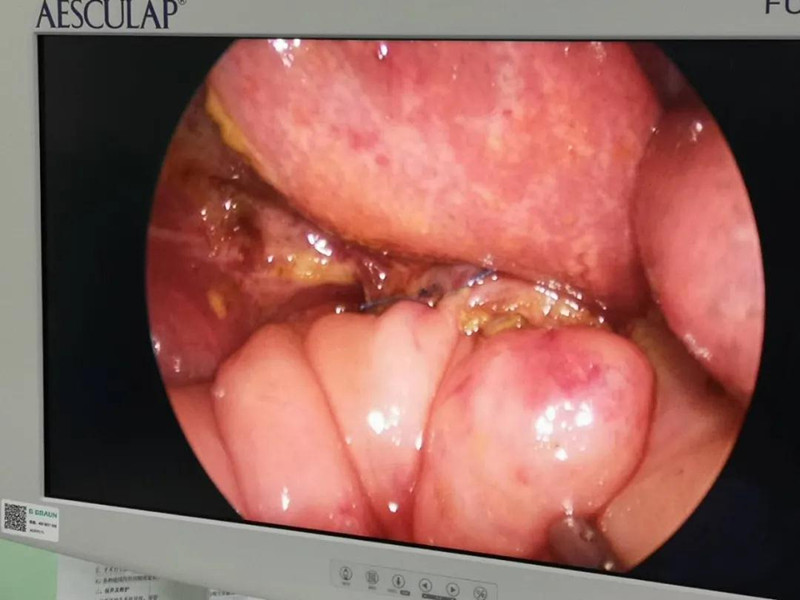

最近半个月,长春市26个月女宝馨馨(化名)脸色不好,全身发黄严重,还伴随发烧。9月23日,馨馨被家人带到德州扑克游戏网 诊治。经检查,馨馨全身发黄是因为患有黄疸,而黄疸的出现是因为胆总管发生病变,“胆总管呈现囊性扩张,下边出口被堵住,胆汁进不到肠腔里,导致孩子出现黄疸、肝功不好、白土便症状。而且胆总管胀大后,还有癌变的风险,”普外、新生儿外科主任崔钊说,馨馨需要尽快手术。为了减少损伤,崔钊主任团队制定的方案是单孔腹腔镜下胆总管囊肿根治手术。

术前准备完毕。 9月25日,馨馨进入手术室。由崔钊主任带队,按照术前设计的方案,经过8个小时的奋战,手术成功了。馨馨肝总管以下病变的胆总管及胆囊全部切除,肝总管断面与肠管吻合接上,让胆汁直接流到肠腔里,帮助消化。如术后不出现胆瘘、肠瘘,没有梗阻,馨馨以后就可以正常生活了。目前馨馨恢复得很好,黄疸渐渐缓解,肝功正常,白细胞也降下来了,排气、排便都没问题,引尿管里也没有异常东西。